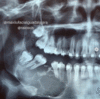

Befunde dieses RÖ-Bild

Panoramaschichtaufnahme. Zystischer Prozess im Unterkiefer links im Bereich der Schaltlücke in regio 36 ohne Lagebeziehung zum Zahnbestand.

Histologie: radikuläre Zyste. Diagnose: Residualzyste [nach Zahn- Extraktion]

Panoramaschichtaufnahme.

Zystischer Prozess im Unterkiefer links mit

Lagebeziehung zum wurzelgefüllten Zahn 37.

Histologie: radikuläre Zyste